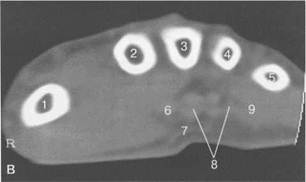

Рис. 19.54. МРТ лучезапястного сустава и кисти в аксиальной плоскости.

б — уровень костей запястья: 1 — крючковидная кость; 2 — головчатая кость; 3 — трапециевидная кость; 4 — кость-трапеция; 5 — группа сухожилий сгибателей; 6 — п. medianus; 7 — группа сухожилий разгибателей.

в — уровень пястных костей: 1 — I пястная кость; 2 — II пястная кость; 3 — IIIпястная кость; 4 — IV пястная кость; 5 — V пястная кость; 6 — сухожилие m. flexor pollicis longus; 7 — ладонный апоневроз; 8 — сухожилия сгибателей; 9 — п. medianus; 10 — m. abductor digiti munimi;11— m. abductor pollicis brevis.